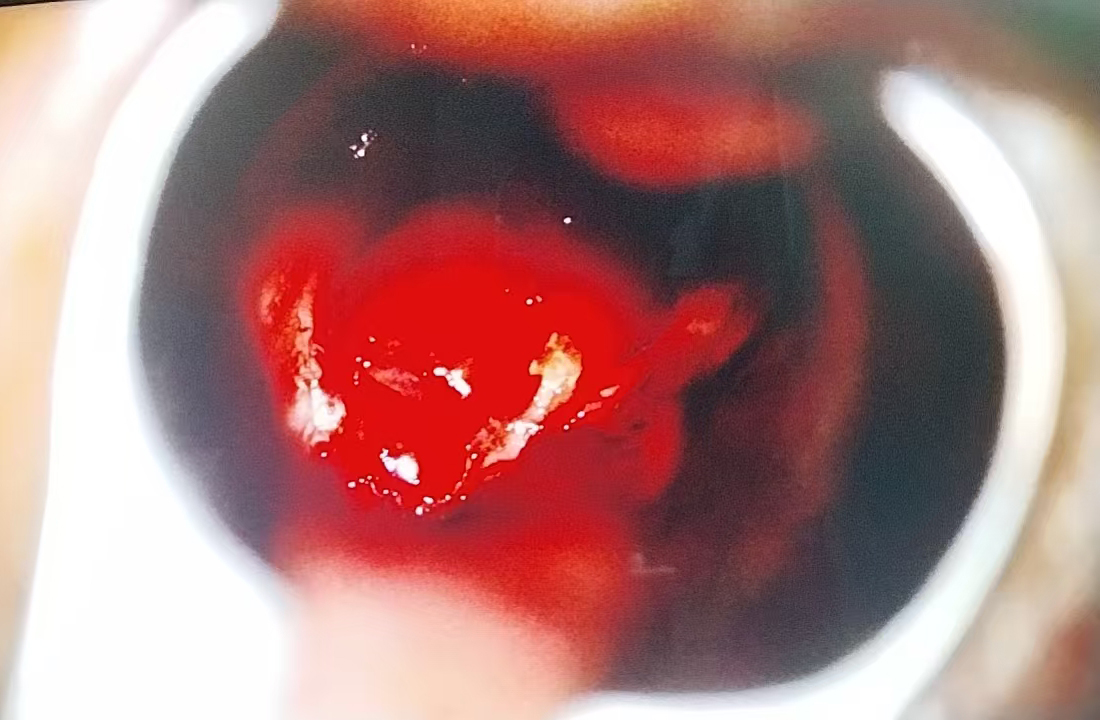

手术当日,在全麻状态下,神经外科团队通过鼻腔这一自然腔道,在神经内镜下清晰暴露术野。精准定位肿瘤位置后,细致操作、逐步切除肿瘤组织,同时妥善修补鞍底硬膜,最大限度保护正常垂体组织,避免损伤周围重要神经与血管。整台手术历时1小时10分钟,术中出血少,无需输血。